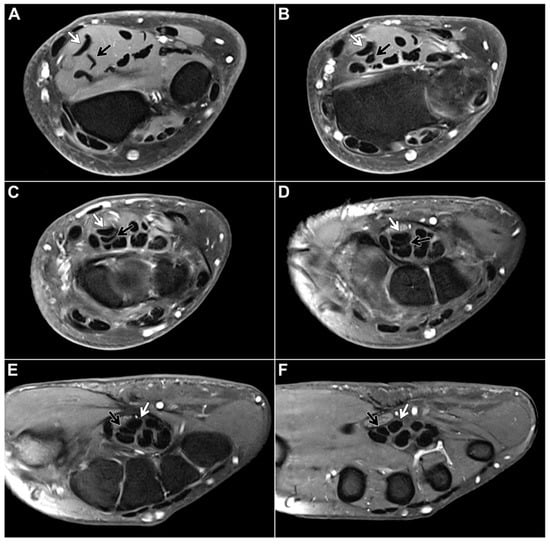

3.3. Verification of Findings in Cadaveric Dissection Studies

In all 11 human body donors assessed for this study, the chiasma antebrachii was present bilaterally in the distal portion of both forearms with the same anatomical configuration that was determined in the vast majority of MRI studies. Figure 4 shows the “standard” FDS tendon anatomy, including the chiasma antebrachii located in the distal portion of the forearm, in two cadaveric specimens (Figure 4).

Figure 4. After careful preparation, the flexor digitorum superficialis (FDS) tendon anatomy is exposed in two body donates. In the dissected distal forearms of both cadaveric specimens (left image: right side; right image: left side), the chiasma antebrachii is marked by the FDS/2 tendon (highlighted in red) crossing under the FDS/3 tendon (highlighted in yellow). (2–5: FDS tendons for digit 2–5).